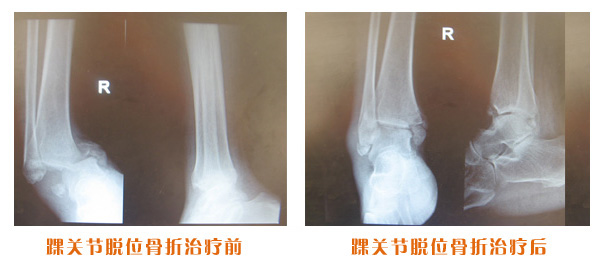

肘關節脫位骨折治療前后對比

踝關節脫位骨折治療前后對比